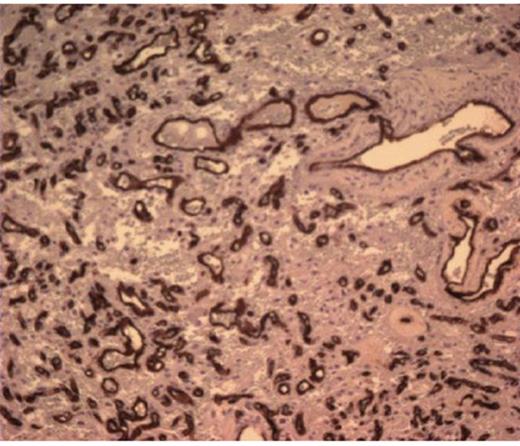

She was taken to the operating the following morning for a bicoronal craniotomy for a gross-total tumor resection with neuronavigation (Fig 2). Pathology was a dural-based WHO Grade 1 supratentorial haemangioblastoma. Microscopic findings demonstrated large vessels and abundant capillary networks, with a cellular proliferation of large stromal cells with clear vacuolated cytoplasm (Fig 3,4,5). There were significant hyperchromatic nuclei and multiple areas of PAS positive pinkish globules (Fig 3,4,5).

10 x Haematoxylin and Eosin stain showing typical microscopic pathology of capillaries and interstitium

No mitoses were identified. No whorls or psammoma bodies were identified. Immunohistochemical findings showed interstitial tumor cells immunoreactive for NSE, factor X111A, and S100. RCC, EMA, Inhibin, GFAP, CAM 5.2, CD 10, and CD 34 were negative on the interstitial cells. CD 34 was positive on the vascular endothelium (Fig 3,4,5). She was discharged home within six post-operative days. She returned to clinic one week later and had no neurological deficits.